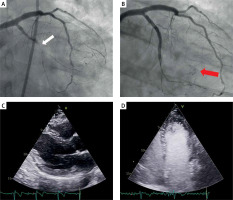

After successful crossing with a Fielder XT-R wire (Asahi Intecc USA, Inc.), recanalization and stenting a chronic total occlusion (CTO) of the left circumflex (LCX) coronary artery (Figure 1 A), distal coronary artery perforation (CAP) was detected (Figure 1 B), but it was not definitive whether this CAP emptied into the pericardium or into a cardiac chamber [1].

Figure 1

A – Initial angiography with chronic total occlusion of the proximal left circumflex artery (white arrow). B – After successful intervention, a coronary artery perforation (CAP) is seen in the distal vessel (red arrow), but it is not definitive whether this perforation emptied into the pericardium (Ellis classification III) or into the left ventricle (Ellis classification III cavity spilling). C – Transthoracic echocardiography showed no evidence of pericardial effusion. D – Contrast-enhanced echocardiography after intravenous injection of the ultrasound contrast agent (UCA), the UCA is absent from the pericardium

The patient remained hemodynamically stable, and transthoracic echocardiography (TTE) showed no evidence of pericardial effusion (Figure 1 C). Despite prolonged balloon inflation, spontaneous sealing was not achieved. To clearly define the direction of the CAP, contrast-enhanced TTE was performed after intravenous injection of 3 ml of sodium hexafluoride-based ultrasound contrast agent (UCA), SonoVue (Bracco International B.V., Amsterdam, NL), followed by 5 ml of a slow normal saline flush [2]. The echocardiographic contrast is used intravascularly and is visualized as hyperechoic spots using dedicated imaging protocols. The identification of contrast in the pericardial space implies active extravasation. No evidence of contrast in the pericardial space was detected in our patient, ruling out active intrapericardial bleeding (Figure 1 D). Following this, anticoagulant reversal with protamine was not performed and the procedure was then completed as it was felt there was no risk of late cardiac tamponade. The patient was discharged 24 h later, with a normal bed-side echocardiography and remains asymptomatic at 6 months’ follow-up. This case illustrates the utility of UCA along with TTE for the definitive diagnosis of CAP leaking into a cardiac chamber and excluding a communication with the pericardium.